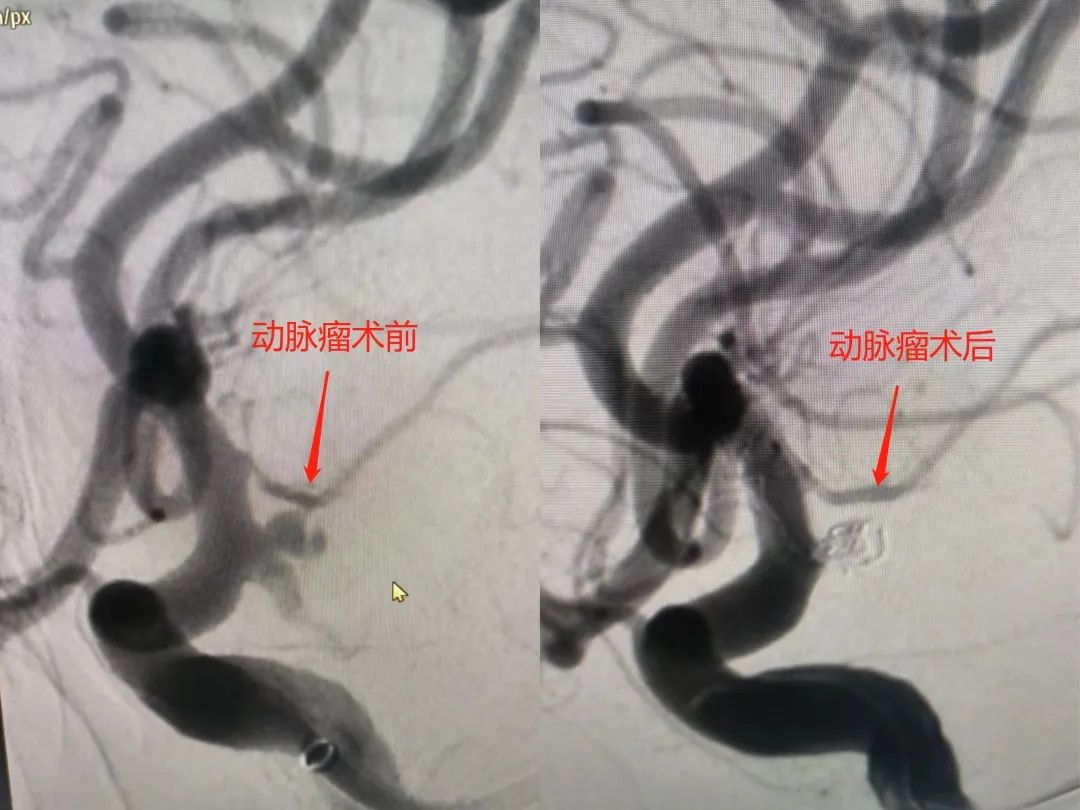

针对这一危急情况,卒中中心技术小组蔡超群、肖科金、高兆玉等立即开展会诊,查看影像资料,详细评估患者病情,确定精准治疗方案。当即向患者家属说明病情凶险程度、救治方案及存在的可能风险。取得家属的理解和信任后,立即行颅内动脉瘤介入栓塞术。术中造影再次证实,夏阿姨左侧后交通动脉瘤直径约3mm,且随时可能再次破裂危及生命,介入团队迅速经微导管利用弹簧圈栓塞动脉瘤,过程顺利,这颗“定时炸弹”的威胁成功解除。